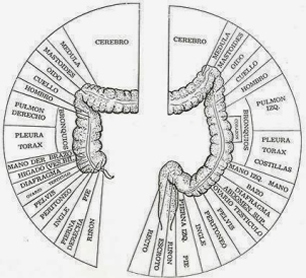

Además, en el colon se localizan terminales nerviosas o puntos reflejos, que inciden en otros sistemas:

- En el sistema nervioso, con el cerebro y la médula espinal como sus piezas principales, que envían señales a otros sistemas del cuerpo para controlar su funcionamiento.

- En el sistema cardíaco, con el corazón y los vasos sanguíneos como protagonistas, que se encargan de transportar sangre con oxígeno y nutrientes hacia todas las células del organismo y de llevar los desechos de éstas hacia los pulmones

- En el sistema endocrino que secreta hormonas, desde distintas glándulas, para que actúen en células específicas que propiciarán un efecto deseado en el organismo.

Los complejos mecanismos por los que actúan estos y otros sistemas, como el digestivo, el respiratorio y el inmunológico, permiten que un cuerpo conserve su estado de salud, gracias al trabajo en equipo ejercido por la unidad funcional básica de nuestro cuerpo: la célula.

Si bien su tamaño es pequeño, su cantidad es numerosa, son 100 millones de engranes trabajando en conjunto, para que los distintos sistemas que componen a esta máquina, lo hagan armoniosamente y cabalmente se cumpla su carácter de Perfecta.

- Estimulacion de los puntos reflejos.

- Cada sistema y órgano del cuerpo está conectado al colon por puntos reflejos.

- Cada sesión de hidroterapia de colon estimula estos puntos reflejos, accionando las partes del cuerpo correspondientes, de una manera beneficiosa similar a la reflexología.